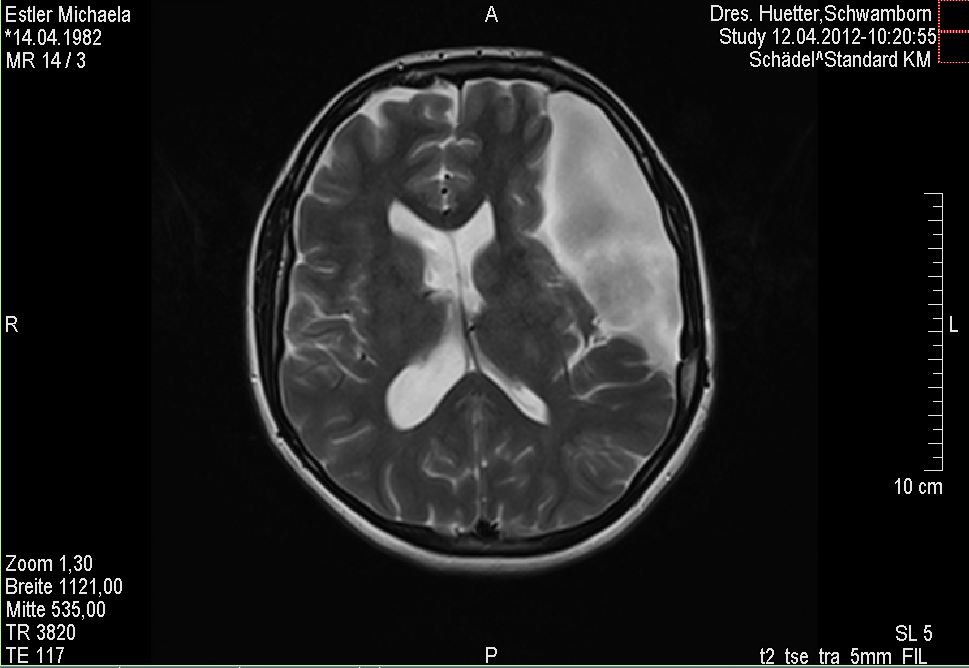

Es war MRT Tag heute. Für diejenigen unter Euch, die es noch nicht wissen sei an dieser Stelle gesagt, dass ich alle zwölf Wochen ein MRT meines Kopfes erstellen lassen muss, damit ich immer weiß, was mein Untermieter in meinem Kopf so schönes treibt, ob er weiterhin Wachstumsambitionen hat usw. Tja und bei solch einer Untersuchung bekommt man ca. nach Hälfte der Zeit einen netten Kontrastmittelcocktail gespritzt, damit manche Dinge auf dem Screening hervorgehoben werden etc. Eigentlich reicht zur Verabreichung dieses Cocktails ein Spritzeneinstichloch in der Armbeuge aus. Aber nun ja, was soll ich sagen? Ich habe es noch nie so wirklich erlebt, dass irgendwer auch auf Anhieb wirklich hinbekommen hat. Und so bin ich bisher jedes Mal mit einigen Einstichlöchern aus der Praxis hinausgelaufen. Ist ja nicht so, dass das überhaupt gar nicht weh tut in der Armbeuge mit so langen Nadeln etc. :haue:

Wie unschwer herauszulesen mag ich diese MRT Tage nicht besonders. Sowieso nicht, wenn dann mein Untermieter auch noch auf den Bildern fast die halbe Hirnfläche ausfüllt. Ich hasse meinen Untermieter echt übelst, aber wie schon längst bekannt werde ich ihn auch in meiner ab Samstag beginnenden neuen Lebensdekade behalten müssen.